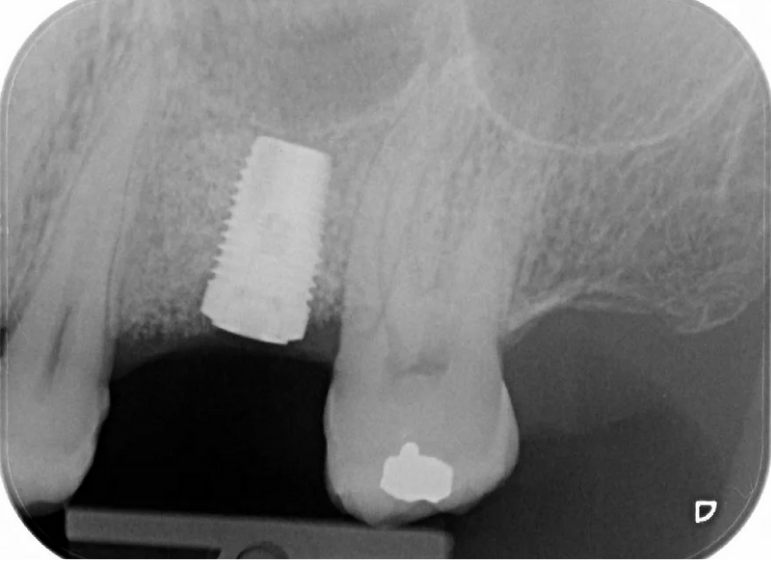

Case 12 – Implants

Molar with failed root filling replaced with an implant.